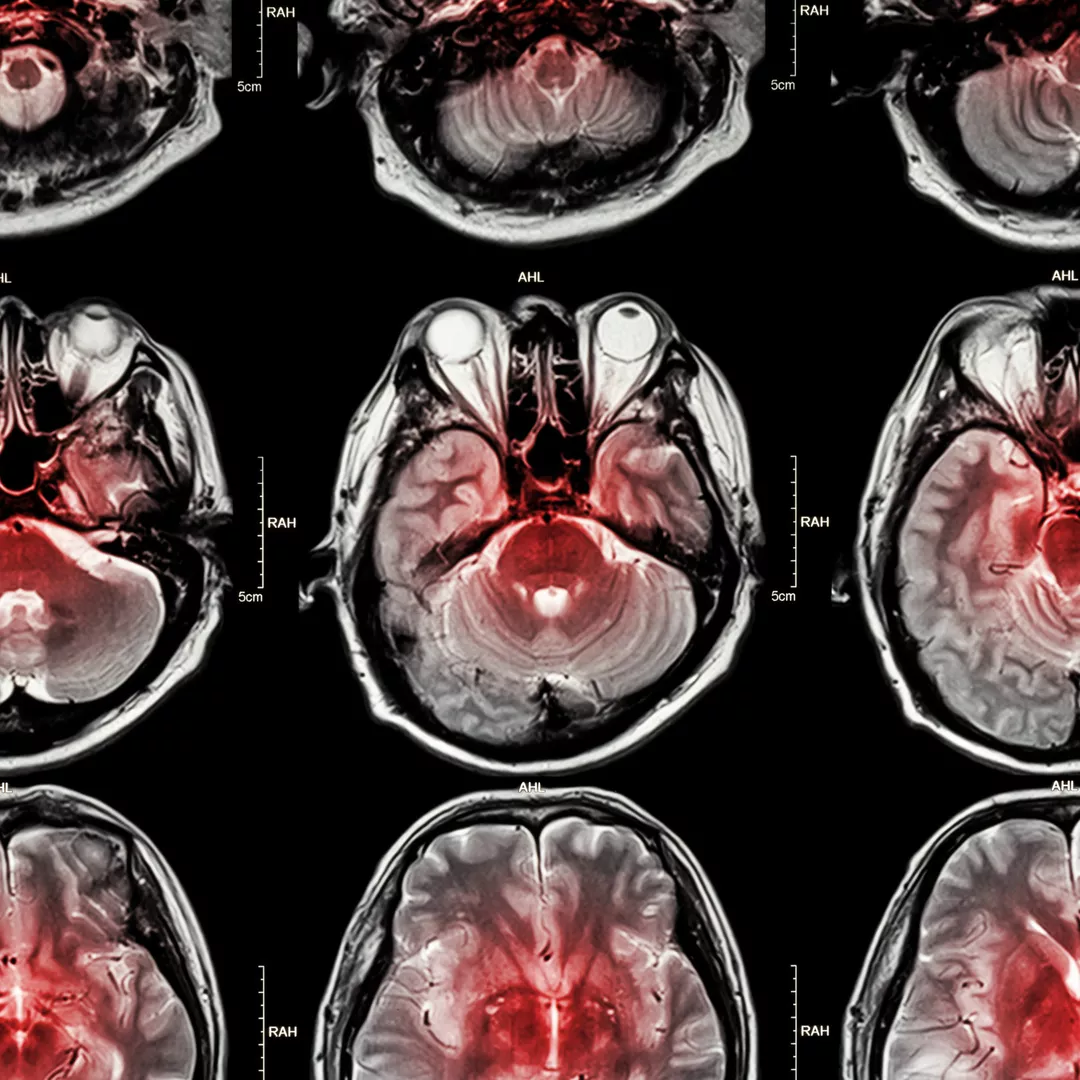

Doctors will conduct some tests to confirm that the symptoms are due to stroke, determine the type of stroke, and find out what area of the brain was affected as well as how severe the impact of the stroke was on the brain. The aim is to discover the cause of the stroke and start treating it.

- brain scans, such as computerised tomography (CT scan) and magnetic resonance imaging (MRI), to show what areas of the brain have been damaged and help determine whether the stroke was ischaemic or haemorrhagic